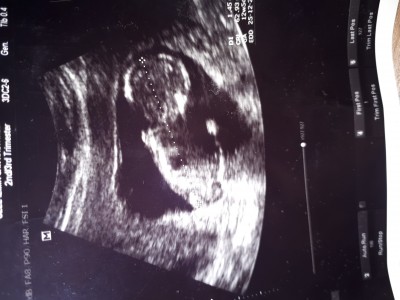

Cinsiyet tahmini yaparmisiniz

Cinsiyet tahmini yapabilirmisiniz

13.hafta

Kiz gibi allah kucagina almayi nasip etsin insallah

Kız gibi

Erkek gibi ama doktor daha iyi bilir tahmin sadece :)

Erkek sanki benim ki de arkadan boyle görünüyor du kızlar biraz daha yuvarlak narin duruyor kemik yapisi

ben yine kemik yapısından kıza benzettim

Kiz gibi Allah tamamını erdirsin cnm

Yapısı erkeğe benziyor hayırlısı olsun